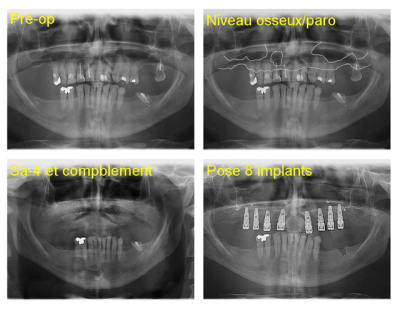

voici 4 scanners montrant la différence de résultat obtenu après un sinus lift.

1 gauche : avant

2 droite : avant

3 droite : après

4 gauche : après

notez surtout qu'à gauche et à droite la consistance est vraiment différente.

1-les sinus ont été fait en même temps

3-date des sinus 30 juin 2011

lequel des deux sinus vous inspire t'il le plus confiance pour une pose d'implant?